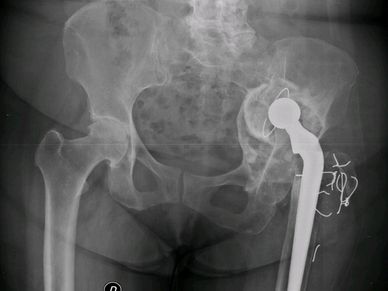

Defecto acetabular complejo, planificacion 3d, artroplastía total de cadera en Rosario - Dr. Pablo Mariani Rovea

Mirá cómo recuperamos la movilidad en un caso de artrosis severa y deformidad acetabular mediante tecnología 3D de alta precisión. Planificación preoperatoria en 3D para cirugía de cadera con artrosis severa e importante deformidad acetabular. Se imprimieron biomodelos en 3D y guías para la correcta colocación de los componentes protésicos. De esta manera, se logró restaurar la longitud de las piernas y se eliminó el dolor invalidante que presentaba el paciente.

Cirugía compleja de reemplazo total de cadera.

Paciente con artrosis severa y deformidad ósea que dificultaba la colocación acetabular. Con tomografía realizamos planificación 3D y diseñamos una guía quirúrgica personalizada impresa en 3D. En quirófano replicamos el plan: posicionamiento preciso del componente y restauración del centro de rotación. La tecnología 3D aporta más precisión, seguridad y predictibilidad en casos complejos.